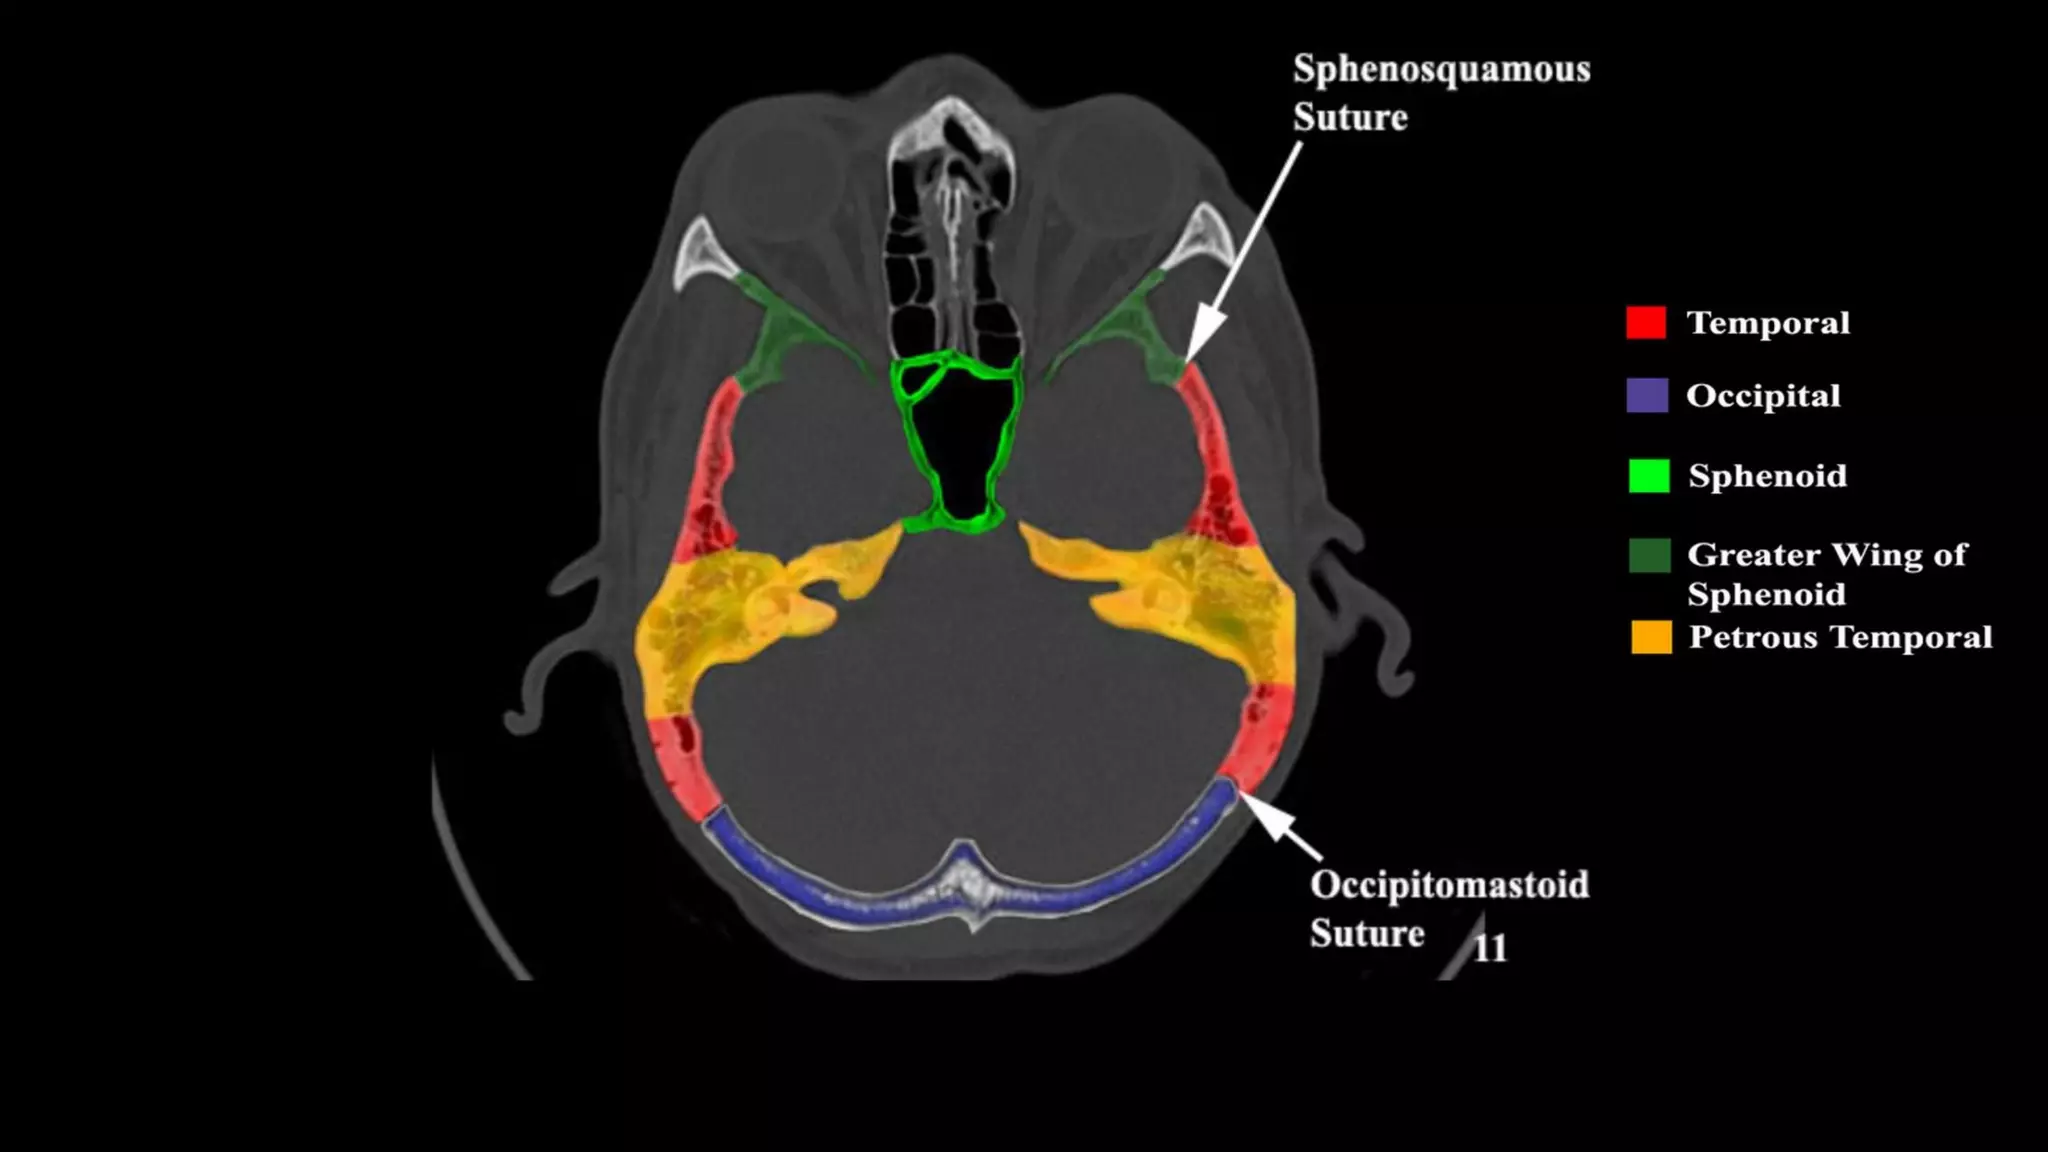

Pseudo-fractures

Extrinsic Fissures &

Sutures